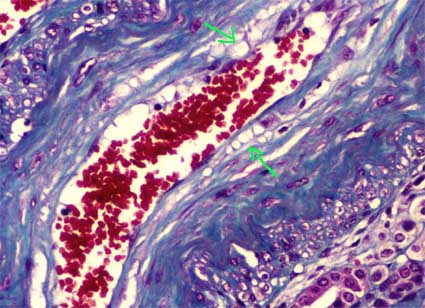

Histopathology

The glomeruli are the main site of injury. There is mesangial expansion and thickening of capillary walls. There are foamy cells in mesangium and capillaries and small holes are seen in the capillary walls, giving an aspect of membranous GN (Figures 10 and 11). You can also see images in double contour and "spikes". There may be segmental sclerosis. In the interstitium we can also find foam cells.

Figure 10. Foam cells, areas with empty appearance and intracapillary hyaline accumulations, which give an unusual appearance to the glomerulus, alterations very suggestive of LCAT deficiency. (H&E, X400).

Figure 11. Irregular capillary walls, with holes. Sometimes we can see spikes that suggest membranous GN; double contours can also be seen, with appearance of membranoproliferative GN. (Methenamine-silver, X400)